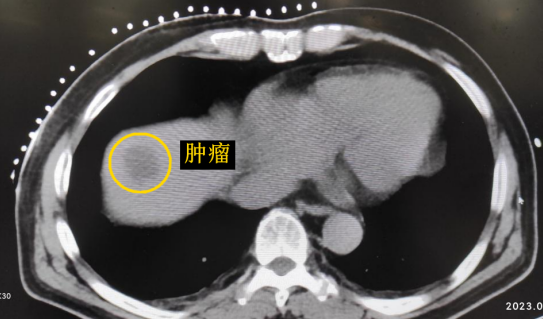

患者老年男性,曾于2021年行結(jié)腸癌手術(shù)。幾月前,發(fā)現(xiàn)肝臟轉(zhuǎn)移瘤,但沒有干預(yù)。近期CT顯示該轉(zhuǎn)移瘤明顯增大,并發(fā)現(xiàn)另一處轉(zhuǎn)移灶。

影像診療科陳寶瑩主任團(tuán)隊(duì)評(píng)估后指出,較大的腫瘤位于肝頂部緊貼膈肌,如果繼續(xù)發(fā)展,腫瘤很可能突破肝包膜侵犯到膈肌,建議及時(shí)干預(yù)。病變緊臨膈肌,如果要完全消融,膈肌損傷的可能性就比較大,與其他局部治療方式比較,冷凍消融對(duì)周圍臟器、血管及神經(jīng)損傷的可能性較小、安全性更高、患者疼痛感較輕,建議通過CT精準(zhǔn)引導(dǎo)下經(jīng)皮微創(chuàng)冷凍消融治療。

CT精準(zhǔn)定位腫瘤